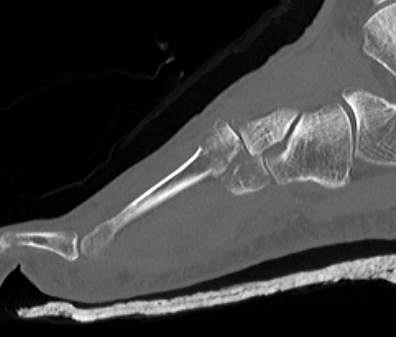

X-ray

AP / Assess medial column

Internal Oblique 30o / Assess lateral column

Lateral / assess dorsal displacement

CT scan

Dorsal displacement of metatarsals

Compression fractures / nutcracker of cuboid